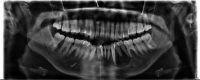

Destructive lesions in the craniofacial region especially in the jawbones, if associated with giant cells, include a spectrum of lesions that pose difficulty in diagnosis. The nature of such a lesion in the jawbones is questionable about whether it is a reactive/benign lesion or aggressive/non-aggressive. Clinical, radiological and histopathological correlation may be a reliable indicator to differentiate between the qualities of the lesion, which directly accounts for effective and individual planning of the treatment. Here we present a case of a woman in her late 20s with an unusual destructive lesion of the mandible.